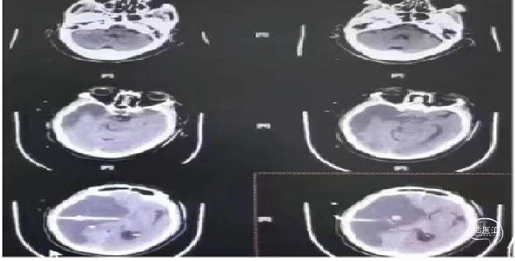

术后8小时出现意识不清,CT示脑水肿明显,给予去骨辨减压重症监护笫3天呈浅昏迷,双下肢肌力3级。第5天,病情加重,预后不良。

患者出现意识不清,病情加重。查CT左侧大脑中动脉区域水肿,低密度改变,中线移位。为大脑中动脉闭塞后改变,恶性脑水肿。

重症脑血管病管理:经甘露醇、白蛋白、3%氯化钠脱水、高压氧、依达拉奉、吡拉西坦脑保护治疗13天水肿消退,脑中线无移位,左侧大脑中动脉区域较前变淡。脑沟脑回显示清楚。